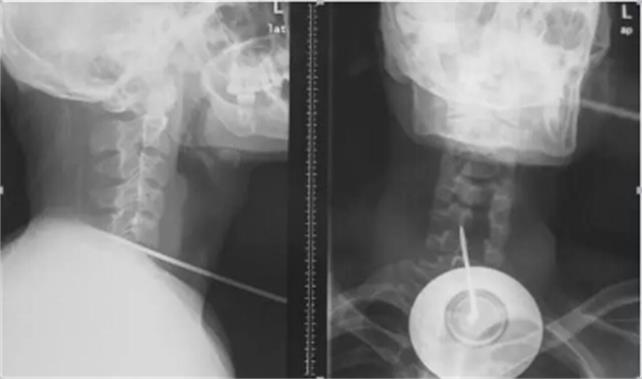

2月13日凌晨3時,上海長征醫(yī)院上演了一場真實(shí)版的“生死時速”。一根長約17厘米的鋼針從患者頸部正中穿入氣管、食管,通過椎體,貫穿脊髓,直達(dá)后路椎板穿出,生命危在旦夕。海軍軍醫(yī)大學(xué)長征醫(yī)院多科專家聯(lián)手合作,緊急手術(shù),展開了一場驚心動魄的生死大援救,成功拔出了奪命鋼針。術(shù)后第二天,患者癱瘓的右側(cè)上下肢功能明顯恢復(fù)。

然而,手術(shù)麻醉成了******道難題。由于鋼針將氣管、食管、脊髓固定在椎體上,無法進(jìn)行麻醉插管,耳鼻咽喉科徐亞平醫(yī)生另辟蹊徑,從鋼針下游,切開氣管實(shí)施插管,避免出血進(jìn)入氣管引起窒息。隨后,麻醉科鄭棟煜迅速完成傷者全身麻醉。首先脊柱二科史建剛教授采用頸部右側(cè)切口,游離皮下間隙,進(jìn)入椎間間隙,只見氣管、食管椎間盤被鋼針貫穿,醫(yī)生細(xì)心顯露頸5、6椎間盤前部,在確保周圍頸部大動脈不被鋼針損傷時,以***快的速度拔除鋼針。突然發(fā)生了驚險一幕,拔出鋼針后,大量的腦脊液和鮮血往外涌出,醫(yī)生迅速鉗夾控制出血,修補(bǔ)硬脊膜,并對損傷嚴(yán)重的頸部兩個骨贅進(jìn)行切除,徹底減輕脊髓壓迫。隨后胸心外科陸昕冶醫(yī)生仔細(xì)尋找食管、氣管壁破損缺口,進(jìn)行了縫合修補(bǔ),止住了食管、氣管漏。經(jīng)過3小時“戰(zhàn)斗”,小陳終于闖過了“鬼門關(guān)”。